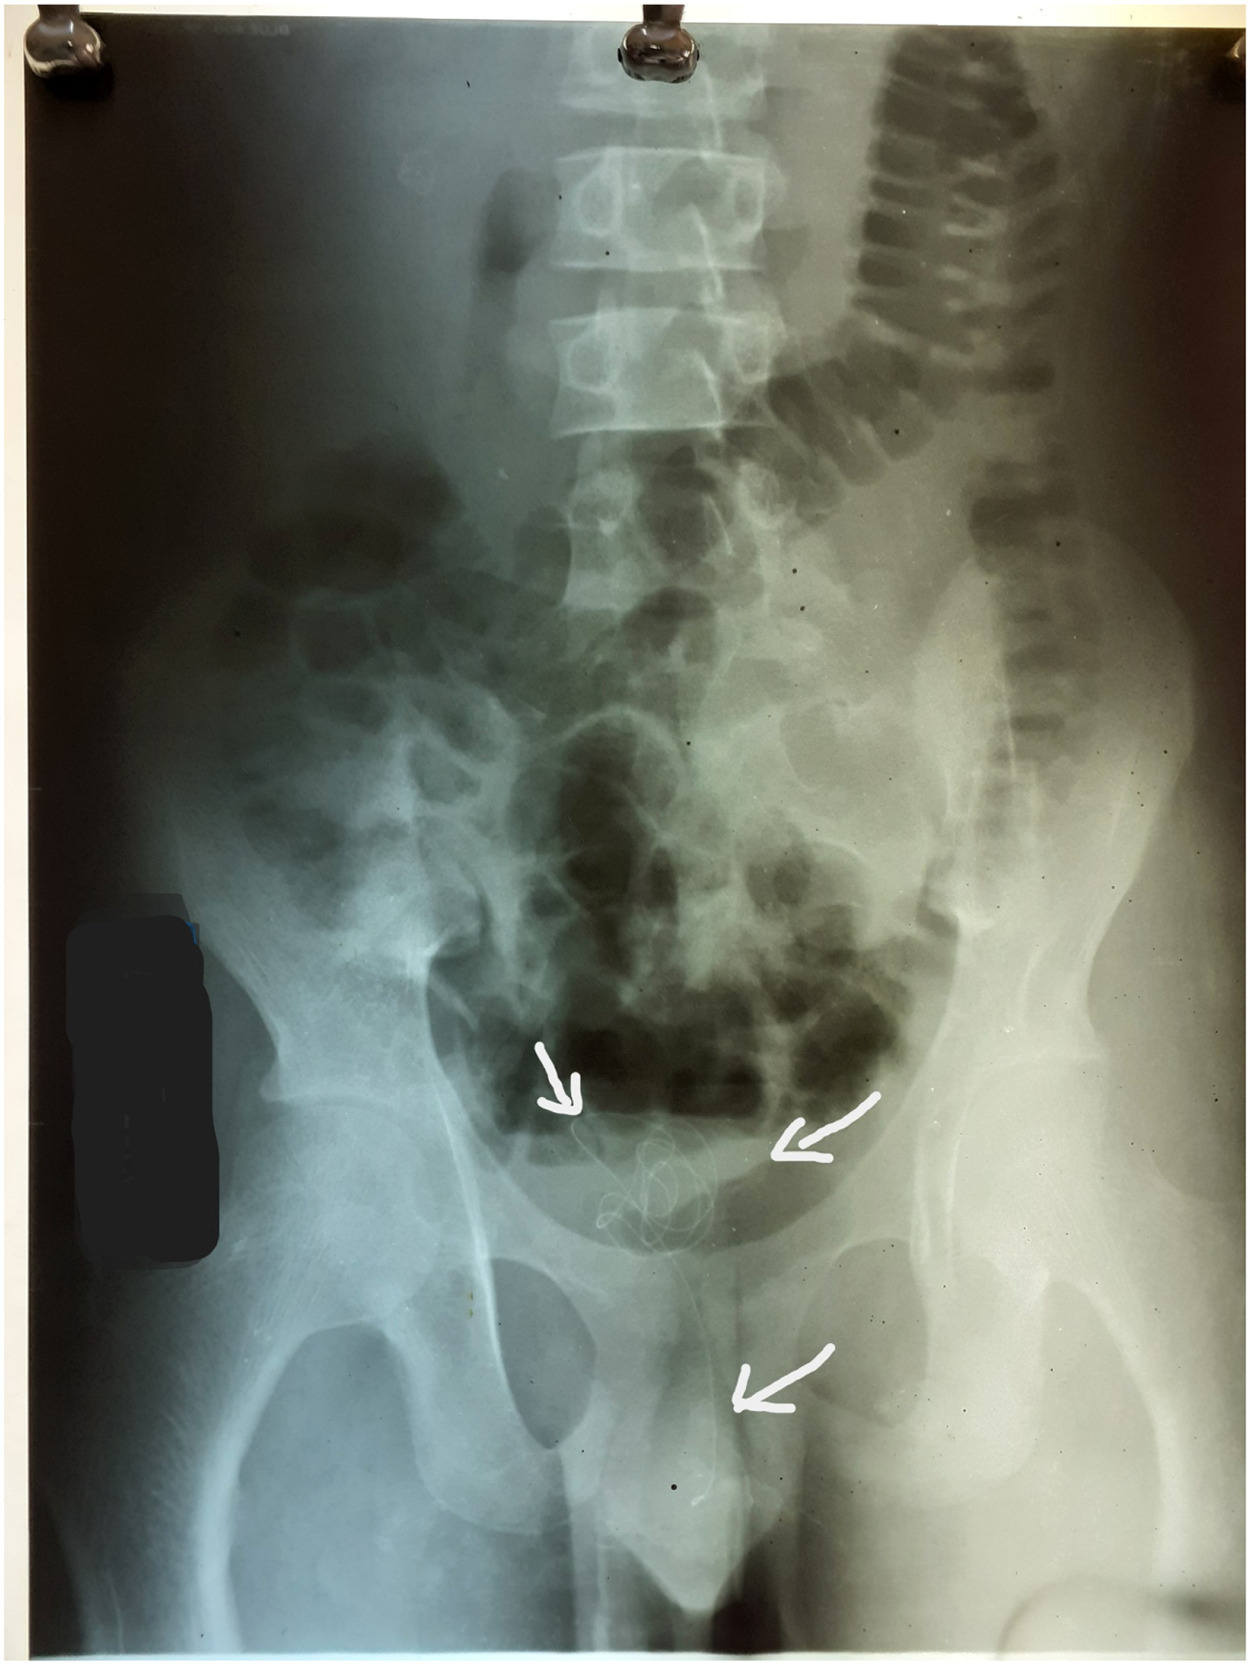

Περίπου 20 εκατοστά ήταν το καλώδιο που αφαίρεσαν οι γιατροί από το πέος ενός 17χρονου στη Σρι Λάνκα.

Ωστόσο, σε κάποια φάση το ώθησε πολύ βαθιά, με αποτέλεσμα να φτάσει έως την ουροδόχο κύστη και να μην μπορεί να το αφαιρέσει.

Ως αποτέλεσμα εκδήλωσε έντονους πόνους στην κοιλιακή χώρα και δυσκολίες στην ούρηση. Είχε επίσης έντονους πόνους καθόλη τη διάρκεια της ούρησης.

Η διαδικασία αφαίρεσης του καλωδίου από το πέος

Οι γιατροί του νοσοκομείου για να αφαιρέσουν το καλώδιο υπέβαλλαν τον 17χρονο σε κυστεοσκόπηση με γενική αναισθησία.